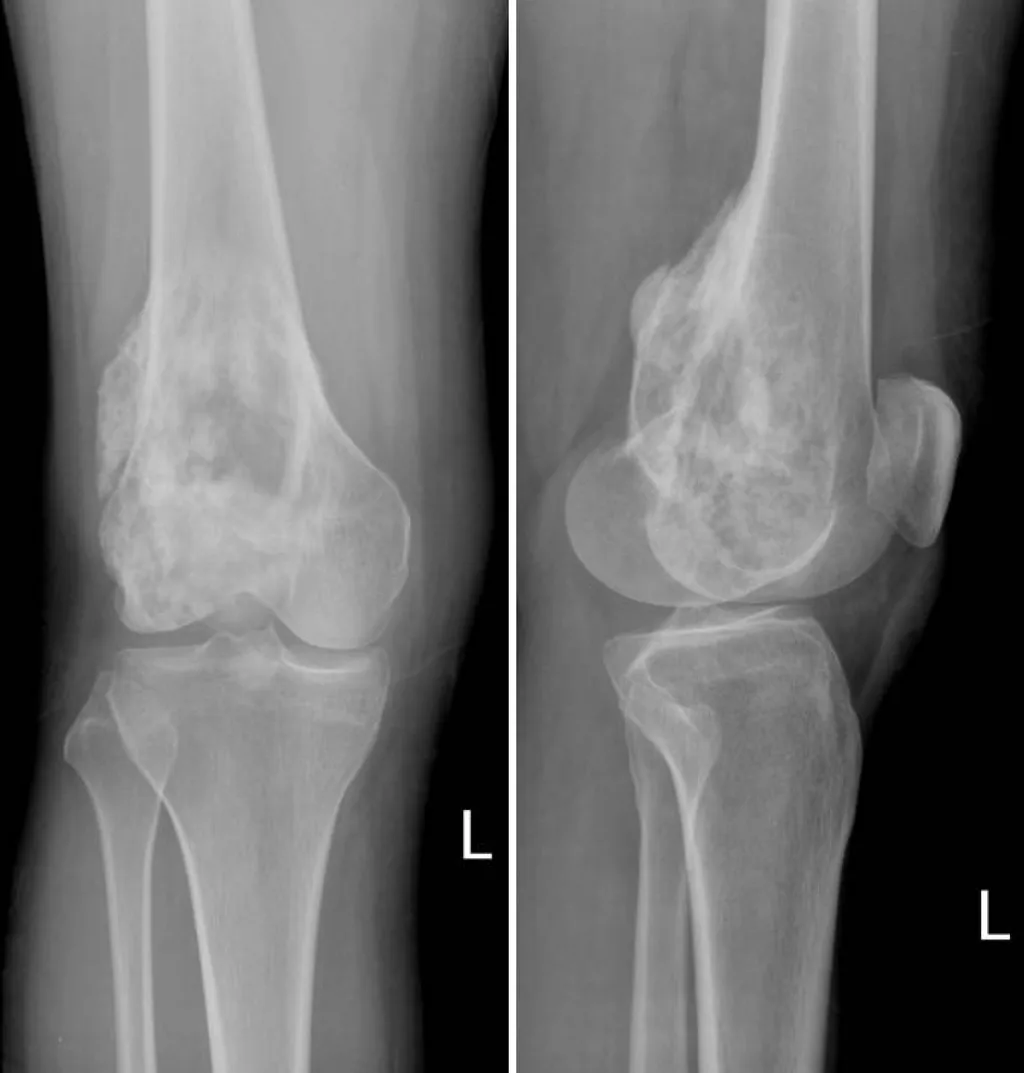

【106-2 醫學(五) 第56題】一位22歲女性抱怨左膝疼痛3個月,問診時發現夜間疼痛加劇。身體檢查發現明顯局部壓痛,觸診時發現有組 織腫塊。膝部X光片如下,此病患最有可能的診斷為: